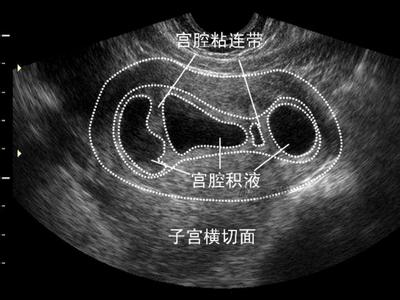

专家详细解析:宫腔粘连

来源:泉州丰泽玛丽医院宫腔粘连是一种比较常见的女性不孕疾病。据相关的报道,宫腔粘连导致的不孕约占整个不孕的10%。泉州玛丽医院的专家介绍,人流刮宫、子宫及生殖道的炎症很容易导致宫腔粘连的发生。患者一旦发现宫腔粘连应该及早到医院进行治疗。泉州玛丽医院专家表示宫腔粘连是指由于创伤或炎症,导致宫颈管、宫腔完全或不完全粘连的一种妇.科疾病,可导致不孕,就算顺利怀孕以后,也容易发生流产。症状按粘连部位不同、程度不同,表现出来的症状也不尽相同。

宫腔粘连的危害及症状

1、周期性的下腹疼痛,影响正常生活:子宫颈管或子宫内口粘连,经血引流不畅,反射性地刺激子宫收缩而导致下腹疼痛。宫颈管粘连时大部分发生于宫颈口处,子宫内膜有周期性变化,组织脱落形成的月经血不能排出,滞留于宫腔或逆流至输卵管、腹腔,出现周期性腹痛。

2、月经异常,影响容颜:宫颈粘连时,因经血不能外流可产生月经减少或闭经等现象,月经的异常可导致色斑、暗疮等问题,影响女性的容貌。

4、生育功能障碍:宫腔粘连可导致不.孕或习惯性流产。据统计,子宫内粘连症的患者中约50%有继发xing不.孕或习惯性流产的病史。